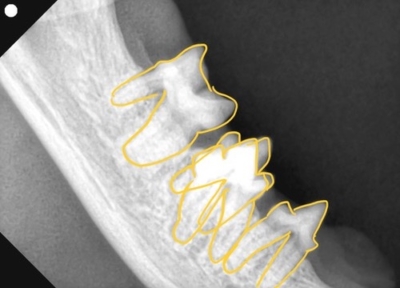

そして歯科レントゲン撮影を行いました。

なにがなにやらわからないと思い、黄色ラインで歯をなぞりました。右上顎です。中央に過剰な歯があり、回転して生えています。

左下顎は正常な数と歯並び

右上顎も同様に中央に回転して生えている過剰歯があります。

左下顎は中央に重なって生えている過剰歯があります。レントゲンで確認しても、乳歯ではなく永久歯と考えられました。これらは過剰歯と呼ばれ、通常より本数が多く歯が生えてきます。かみ合わせが悪くなり、また歯間が狭くなり歯垢がつき、歯周病になりやすいです。そのため、不必要と思われる歯を抜歯しました。また、歯肉の増殖している部分を一部切り取り病理検査用の検体とし、それ以外の部分はメスで切除し正常に近い歯肉の形状に近づけました。